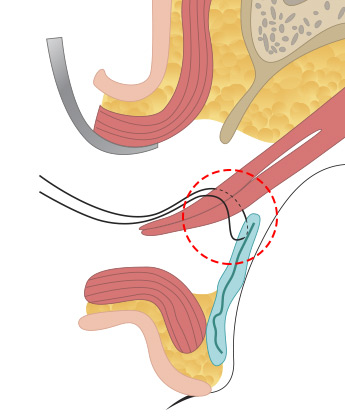

근육과 근막이 안검판이라는 조직에 붙어 있는데 안검하수의 정도에 따라서 경미한 경우는 근막의 길이를 축소해서 다시 붙여주는 상안검거근막 수술을 해주고, <br>

중증도의 경우 뮬러 근육을 당겨서 안검판에 고정하는 수술을 하고 중증인 경우에는 상안검거근을 아래로 당겨서 축소해주는 수술을 합니다.

올림근 널힘줄 중첩술

올림근 널힘줄 중첩술

올림근 널힘줄 중첩술 -

뮬러근 중첩술

뮬러근 중첩술 -

뮬러근 전진술

뮬러근 전진술 -

뮬러근과 올림근, 널힘줄을

뮬러근과 올림근, 널힘줄을

동시에 전진술로 교정